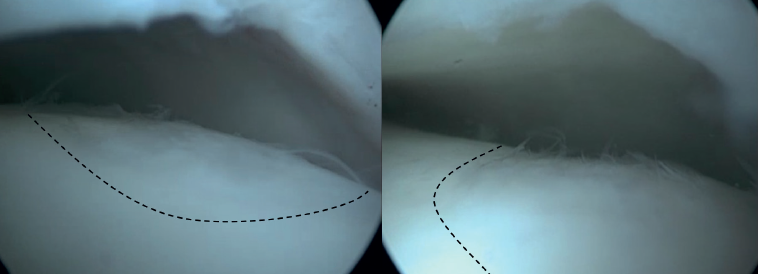

Las técnicas de fijación han demostrado éxito clínico y radiológico en 8 de cada 10 pacientes y el éxito también se ha mantenido a largo plazo (Figuras 5 y 6). Dado que estas técnicas preservan el cartílago hialino y proporcionan una cicatrización superior del hueso subcondral, resultan ventajosas frente a otras opciones de tratamiento quirúrgico de las OLT, cuando son factibles(39,41).

Figura 5. Tomografía computarizada preoperatoria (A y B) y postoperatoria al año (C y D) de un paciente tras la fijación.